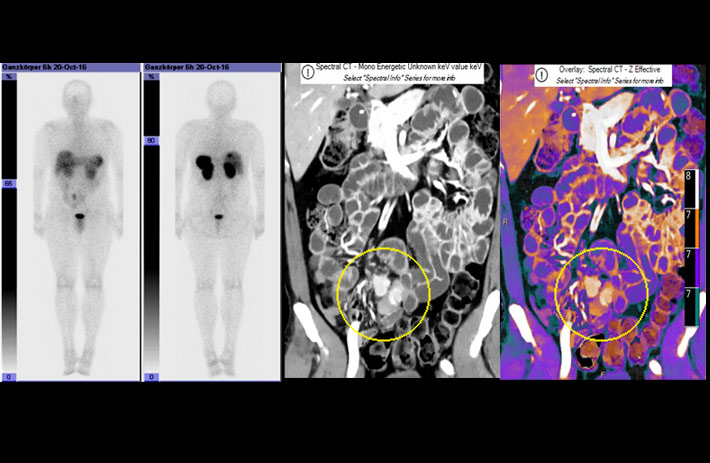

Mit dem Spektral-Detektor-CT werden Spektraldaten automatisch bei jedem Scan erfasst. Die Informationen stehen jederzeit auf der Scankonsole, der CT-Workstation sowie an jedem PACS-Arbeitsplatz zur Verfügung, sodass es nicht notwendig ist, den Patienten erneut zu scannen, bspw. wenn initial zufällige Anomalien festgestellt wurden. Dadurch profitieren Anwender durch eine höhere Diagnosesicherheit und weniger Nachuntersuchungen auf anderen bildgebenden Systemen. Unsere Fallsammlung zeigt, welchen klinischen Mehrwert der Spektral-Detektor-CT in unterschiedlichsten Anwendungsbereichen in der klinischen Routine bringt. Jede Woche gehen neue Fälle live.